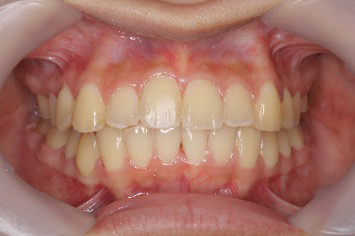

■症例3

Before

After